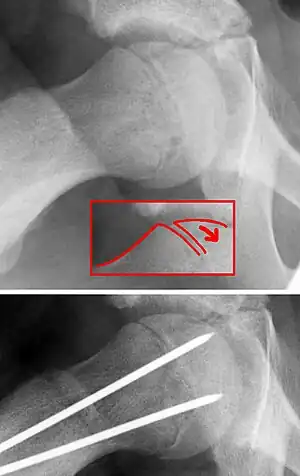

| X-ray showing a slipped capital femoral epiphysis, before and after surgical fixation. | |

The diagnosis requires x-rays of the pelvis, with anteriorposterior (AP) and frog-leg lateral views.[12] The appearance of the head of the femur in relation to the shaft likens that of a "melting ice cream cone", visible with Klein's line. The severity of the disease can be measured using the Southwick angle.

The disease can be treated with external in-situ pinning or open reduction and pinning. Consultation with an orthopaedic surgeon is necessary to repair this problem. Pinning the unaffected side prophylactically is not recommended for most patients, but may be appropriate if a second SCFE is very likely.[12]

Once SCFE is suspected, the patient should be non-weight bearing and remain on strict bed rest. In severe cases, after enough rest the patient may require physical therapy to regain strength and movement back to the leg. A SCFE is an orthopaedic emergency, as further slippage may result in occlusion of the blood supply and avascular necrosis (risk of 25 percent). Almost all cases require surgery, which usually involves the placement of one or two pins into the femoral head to prevent further slippage.[13] The recommended screw placement is in the center of the epiphysis and perpendicular to the physis.[14] Chances of a slippage occurring in the other hip are 20 percent within 18 months of diagnosis of the first slippage and consequently the opposite unaffected femur may also require pinning.

The risk of reducing this fracture includes the disruption of the blood supply to the bone. It has been shown in the past that attempts to correct the slippage by moving the head back into its correct position can cause the bone to die. Therefore the head of the femur is usually pinned 'as is'. A small incision is made in the outer side of the upper thigh and metal pins are placed through the femoral neck and into the head of the femur. A dressing covers the wound.